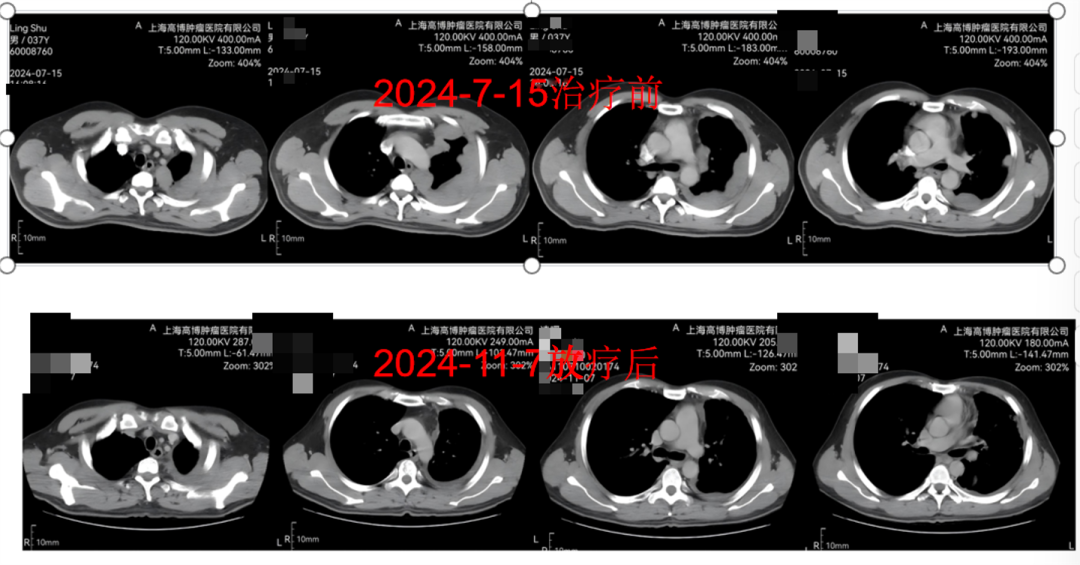

病例3:胸腺癌复发转移的精准守护

凌先生(化名),38岁,不幸罹患胸腺瘤,且多次复发,胸廓广泛转移伴胸腔积液。在多次手术和化疗耐药后,他来到了我院,寻求新的治疗希望。

TOMO放疗的360度螺旋断层照射技术,能够根据肿瘤的形状和大小,动态调整照射剂量,特别适用于形状复杂或位于关键器官附近的肿瘤。其治疗范围广,可同时治疗多个病灶,尤其适用于多发转移瘤或大面积肿瘤的治疗。对于凌先生的胸腺癌复发转移情况,TOMO放疗不仅能够精准打击肿瘤,还能最大限度地保护周围正常组织,提高治疗效果和患者的生活质量。

TOMO剂量分布图

治疗前后对比